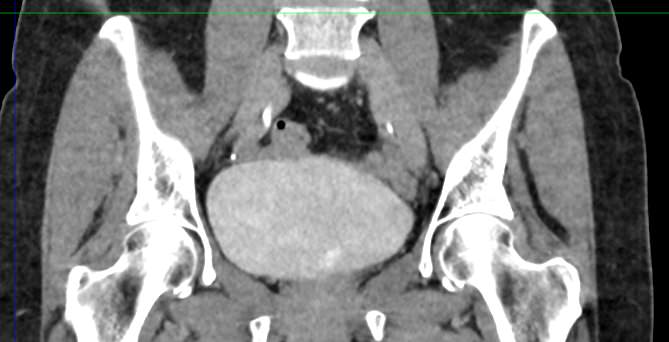

Мультиспиральная КТ мочевого пузыря является частью протокола обследования органов малого таза. Это высокоинформативный рентгенологический метод исследования, позволяющий детально визуализировать мочевой пузырь, нижнюю часть мочеточников, внутренние половые органы, прямую кишку.

Зачастую подобное исследование проводится при мочекаменной болезни (МКБ) для выявления конкрементов, определения их положения, размеров и плотности. Локализация конкремента существенно влияет на терапевтическое лечение МКБ, а наличие дивертикулов стенки мочевого пузыря на возможность самостоятельного выхода камня.

Также при данном исследовании возможно выявить утолщение стенки мочевого пузыря, что при диффузных изменениях может соответствовать проявлениям цистита, а локальные или неравномерные утолщения – характеризовать патологический процесс обусловленный новообразованиями.

Для улучшения визуализации патологических образований, в частности, при подозрении на опухолевый процесс, проводится внутривенное болюсное контрастирование. Методика контрастного усиления основана на введении в вену контрастного препарата, который в большей степени накапливается в патологически измененных участках и обеспечивает их яркую визуализацию на фоне здоровых тканей. Контрастирование дает возможность определить врачу границы опухоли, оценить степень прорастания в соседние органы и ткани, выявить опухоли минимальных размеров (как первичного, так и метастатического характера).

Мультиспиральная КТ используется для диагностики аномалий развития мочевого пузыря, травматических повреждений, воспалительных заболеваний и опухолевых процессов органов малого таза. Преимуществами данного исследования является высокая скорость сканирования и доступная цена. Однако в ряде случаев может быть более предпочтительно выполнение магнитно-резонансной томографии, которая обладает высокой чувствительностью и информативностью для обследования органов и мягких тканей малого таза. В клинике «Доступная медицина» обследование мочевого пузыря входит в протокол МРТ малого таза и его можно пройти на нашем современном оборудовании экспертного уровня